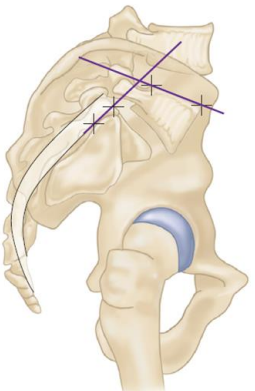

• Como traçar o ângulo de escorregamento (ângulo de Boxal) e o que ele prediz?

• Divergência na literatura

A

• 1° linha tangente, junto a região posterior ao sacro

• 2° linha perpendicular à 1°, passando pelo sacro

• 3° linha paralela ao platô inferior de L5

• Ângulo entre a 2° e 3° linha → ângulo de escorregamento

• Valor preditivo para escorregamento > 30°

Ângulo de deslizamento é a medida da cifose no local

• Como traçar o ângulo lombossacro e o que ele prediz?

• 2° linha paralela ao platô superior de L5

• Ângulo entre a 1° e 2° linha → ângulo lombossacro

• Valor preditivo para escorregamento > 10°